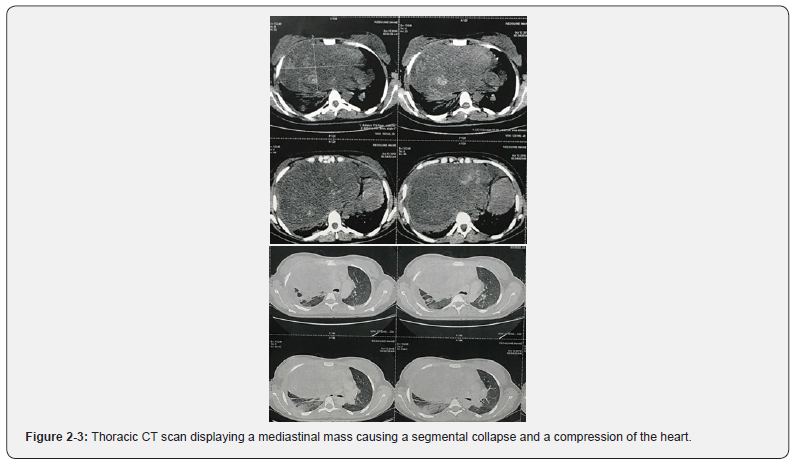

A thoracic CT scan was performed showing a large right mediastinal mass measuring 174x40x86 mm, causing an upper right segmental collapse and significant compression of the cardiac chambers, as well as a moderate pleural effusion (Figure 2 & 3). The transthoracic echocardiography objectified a 35mm pericardial effusion over the right heart chambers, with a preserved LV function (Figure 4).